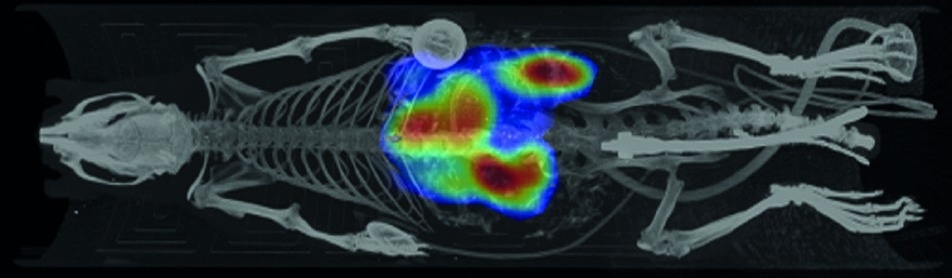

The seamless in-line mode allows you to perform optical tomography with the help of MILabs’ unique bioluminescence tomographic ("BLT") and/or fluorescence tomographic ("FLT") imaging functionalities. Segmented CT images from the same animal(s) are used to guide 3D/4D BLT and/or FLT images for more accurate reconstruction and quantification of deep tissues and dark organs.

Figure 1: Anatomical co-registration of 2D optical and 3D CT using Perspective MIP. Image credit: MILabs